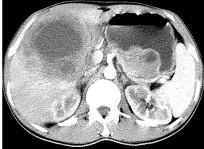

问题 女,61岁,上腹部疼痛一个月,食欲减退,消瘦,CT所见如图,最可能的诊断是 ( )

选项 A.肝脓肿 B.肝转移瘤 C.胃癌肝转移 D.肝包虫病 E.原发性肝癌

答案 C